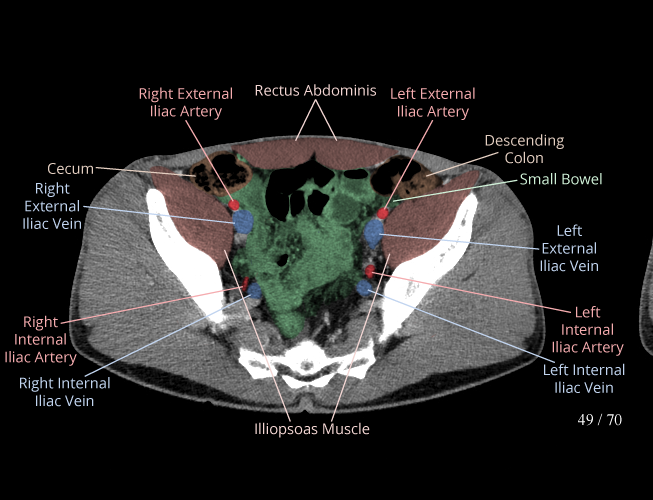

Body

Covers abdominal CT anatomy.